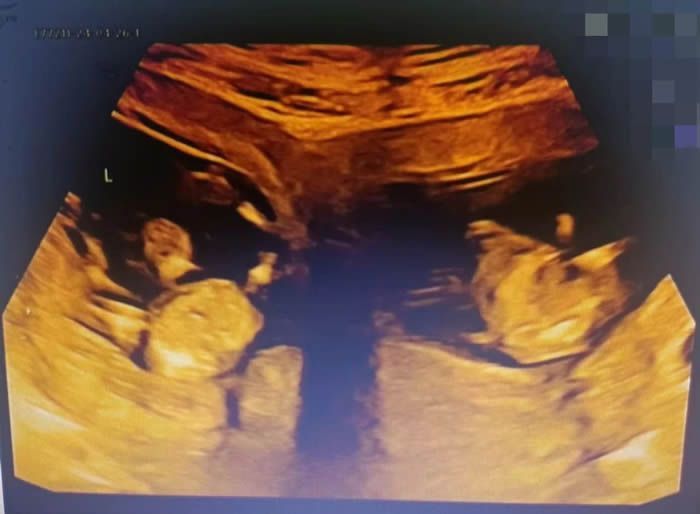

更令人意外的是,早孕期超聲提示,曉曉腹中竟有兩個胎兒,且兩個孩子各居“一室”,互不干擾。“在我近30的職業(yè)生涯中,還從未遇到過雙子宮雙胞胎的孕婦。雙子宮女性妊娠風(fēng)險非常多,很可能會出現(xiàn)早產(chǎn)、胎兒生長受限、子宮破裂等情況,每種風(fēng)險都不容小覷。”產(chǎn)科九病區(qū)主任吳惠瑩如是說。

7點(diǎn)50分,一場生命與時間的賽跑拉開序幕。與普通的雙胎剖宮產(chǎn)手術(shù)不同,此次手術(shù)需要分別在曉曉的兩個子宮上切口取出胎兒。

早早等在一旁的新生兒科醫(yī)生立刻為兩個孩子進(jìn)行檢查,隨后轉(zhuǎn)入新生兒病房進(jìn)行救治。為了預(yù)防產(chǎn)后出血,取出龍鳳胎后,沙小龍醫(yī)生第一時間用藥促進(jìn)子宮及時收縮,兩個子宮緊緊貼在一起,形成了一個完整的心型。